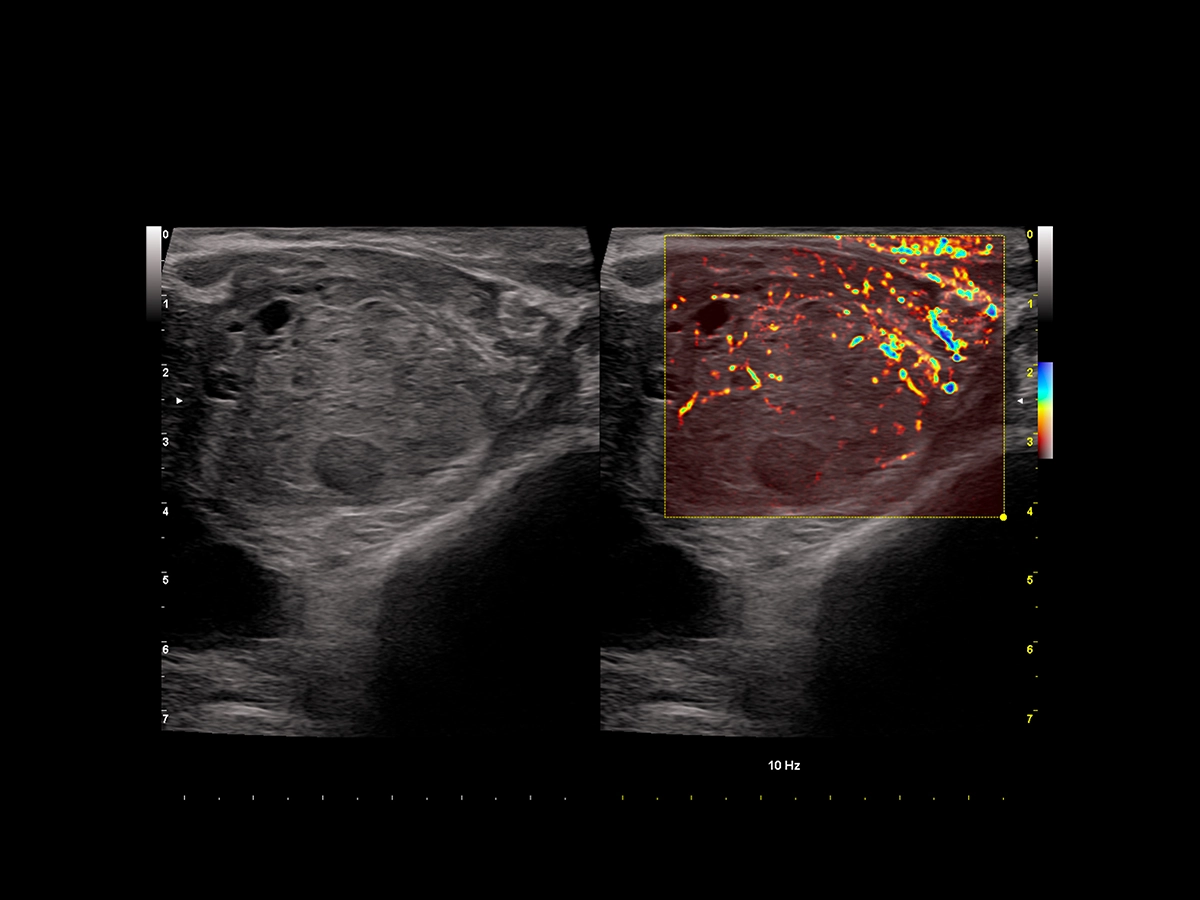

microV shows vascularization and improves the visualization of slow blood flow in tiny vessels.

An adaptive algorithm identifies the blood flow signals and separates them from background tissue and motion artefacts. By eliminating background noise, microV technology enables an advanced hemodynamic evaluation with maximum sensitivity and spatial resolution.

microV to study the micro-vascularization of the suspicious area